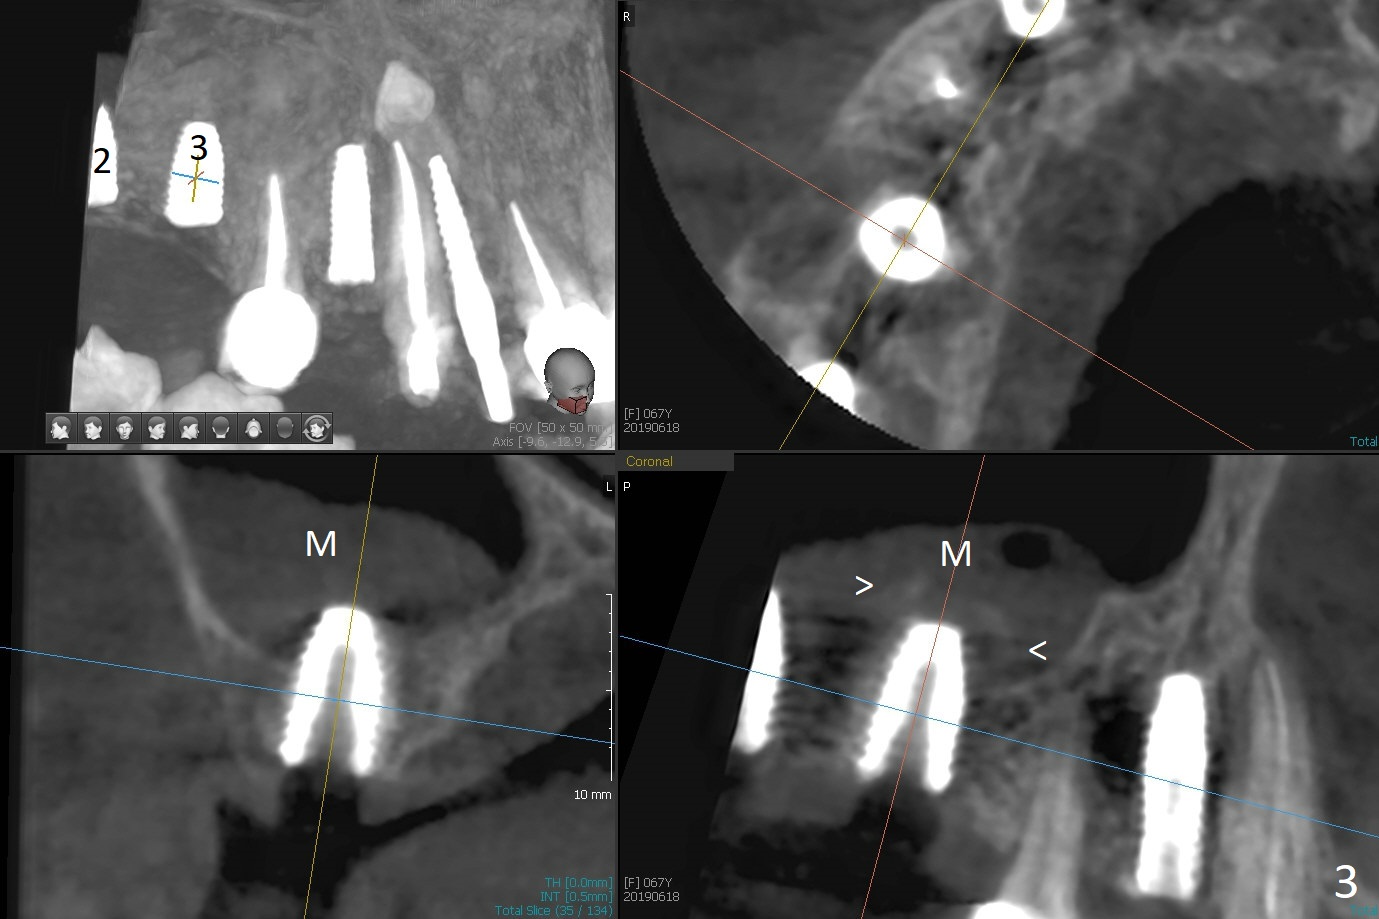

Two of 5x8.5 mm implants are placed at #2 and 3 with sinus lift using water ballooning technique; to avoid invading the neighboring root tips, an intraop PA is taken with a 2.2x11.5 mm drill at #5 (Fig.1). When a 2.5x11.5 mm 1-piece implant is placed at #7, there is 2.4 mm clearance from the impacted tooth (Fig.2). Following 1 mm deeper placement of the 1-piece implant, CT is taken to make sure that the threads are completely covered palatally (Fig.5 P). Interesting is that the sinus membrane is thickened at #2 and 3 (Fig.3 M), as compared to the clear sinus before surgery (Fig.3'). Bone graft is limited in the sinus (Fig.3 arrowheads). The implant at #5 (3.5x11.5 mm) is precisely placed subcrest bucco(B)-palatally (Fig.4). Since the limited field viewed CT does not cover the implant at #2 (Fig.3), immediate postop PA is taken (Fig.6). In fact all of the implants are placed subcrestal, as shown by intraoral X-ray 4 months postop (Fig.7-9). The abutments at #2, 3 and 5 are retorqued (30 Ncm) after crowns' try in and adjustment (Fig.10,11). There is a vertical gap between the implant and abutment at #2 (Fig.11 ^) and a horizontal one at #5 (<). There is apparently no bone loss 1 year 5 months post cementation (Fig.12).